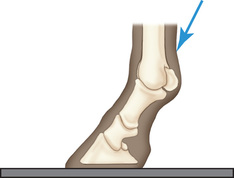

The most significant safety action is to increase one's distance from the primary beam through the use of a cassette holder (Fig. 24.3) and the use of a tripod to hold the x-ray unit if space and circumstances allow. Because the construction of x-ray machines does not allow the primary beam to be centered less than about 10 cm (4 inches) from the ground, a positioning block is needed to raise the affected foot (Fig. 24.4) for most views of the foot and pastern.

If using a foot block, have it high enough so that the beam can be directed in a horizontal plane on the area of interest. Ideally, the block should have a slot to support the cassette close to the limb to minimize distortion (Fig. 24.4D). If only the lateromedial view of the digit is needed, then shoe removal, sole cleaning, and foot trimming are not essential. For equal weight-bearing, both front feet should be on a foot block. If only the affected foot is placed on the block, improper pressure of the distal limb joints may affect the accuracy of the diagnosis.